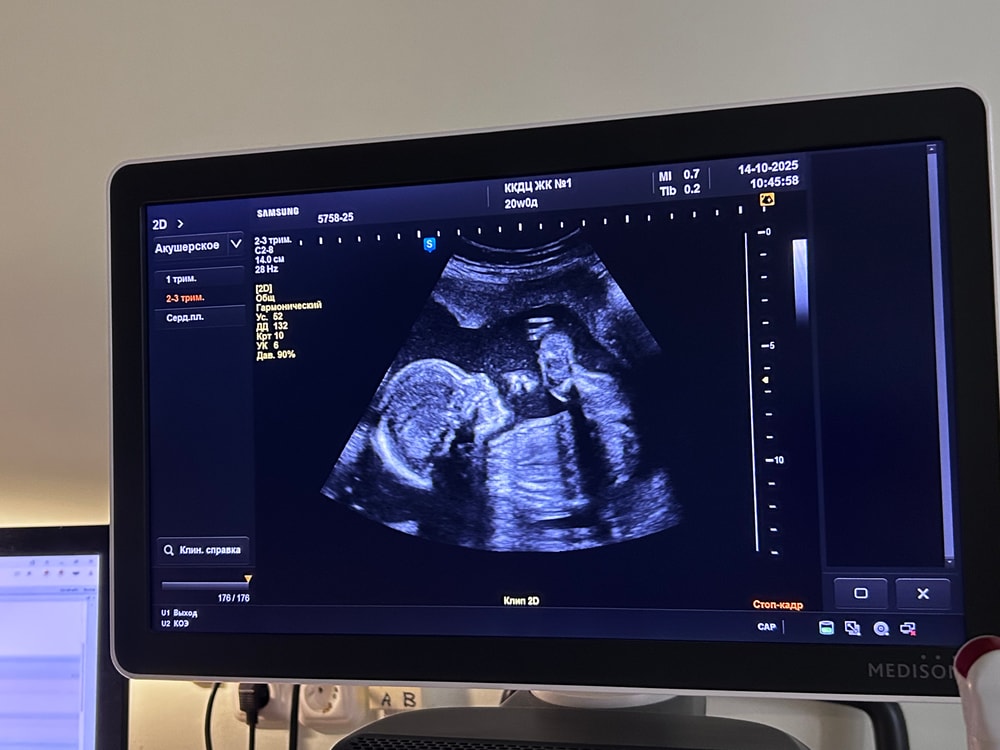

20 недель. Мой экватор 👼🏻✨

Были на повторном скрининге, сегодня ровно 20 недель, по узи на неделю она так и опережает, всё хорошо, всё в норме

375 грамм моё чудо весит ❤️